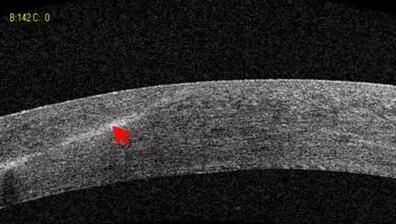

白内障篇

1:白内障混浊晶体观察

2:人工晶体位置观察

易游体育课堂:后节频域OCT前节模块的运用14.jpg

易游体育课堂:后节频域OCT前节模块的运用15.jpg